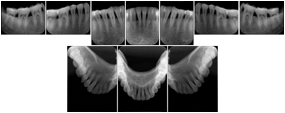

5 Bitewing Dental Image Layout

DL-S007A

Reference:

20

Standard

18, 17, 16, 48,

47, 46

21

17, 16, 15, 14, 13, 47, 46, 45,

44, 43

22

Pedodontic

12, 11, 21, 22,

32, 31, 41, 42

23

23, 24, 25, 26, 2733,

34, 35, 36, 37

24

26, 27, 28, 35, 36,

37, 38